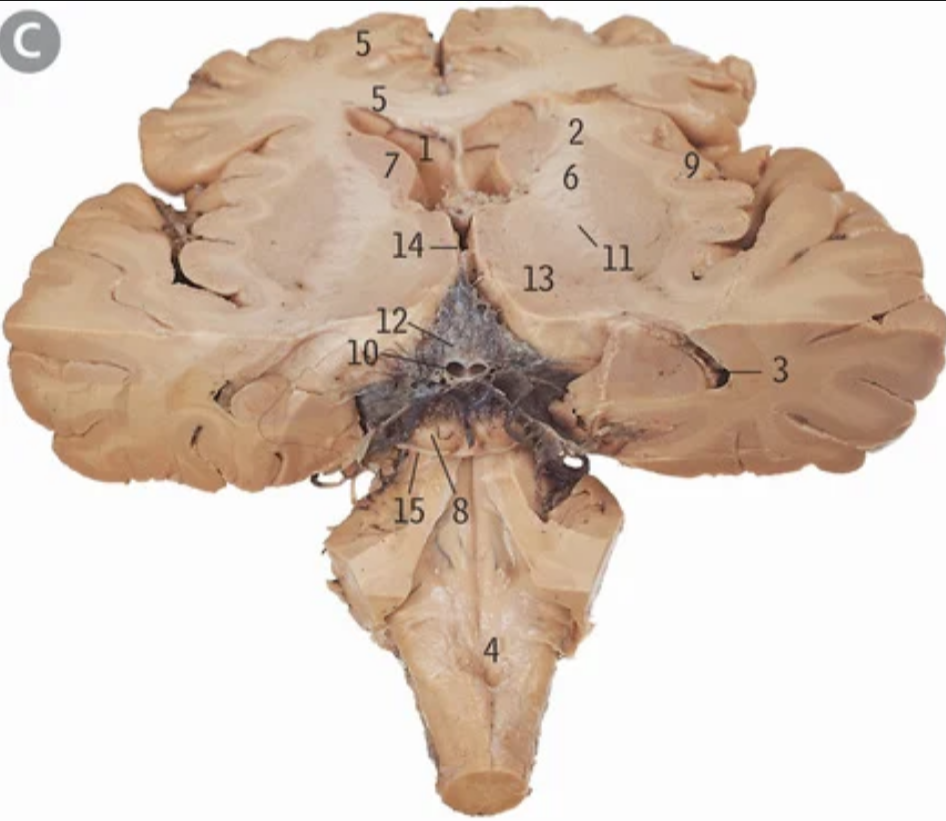

4th/fourth ventricle

Floor of fourth ventricle

What forms the floor of the 4th ventricle

Medulla caudally, pons rostrally

What forms the roof/dorsal wall of the 4th ventricle

Cerebellar peduncles

24

Middle cerebellar peduncle

What is the 4th ventricle connected to the subarachnoid space of the cerebellopontine angle by?

Lateral aperture of 4th ventricles/Foramen of Luschka

X

Lateral aperture of 4th ventricle/foramen of luschka

Median aperture of 4th ventricle/foramen of magendie

What does the median aperture of the fourth ventricle connect the 4th ventricle to which part of the subarachnoid space?

Cisterna magna

2

What are the lateral walls of the rostral part of the 4th ventricle made up of?

Superior and inferior cerebellar peduncles

Superior cerebellar peduncle

Inferior cerebellar peduncle

In the rostral pons, where do the walls of the 4th ventricle converge at

Pontomesencephalic junction